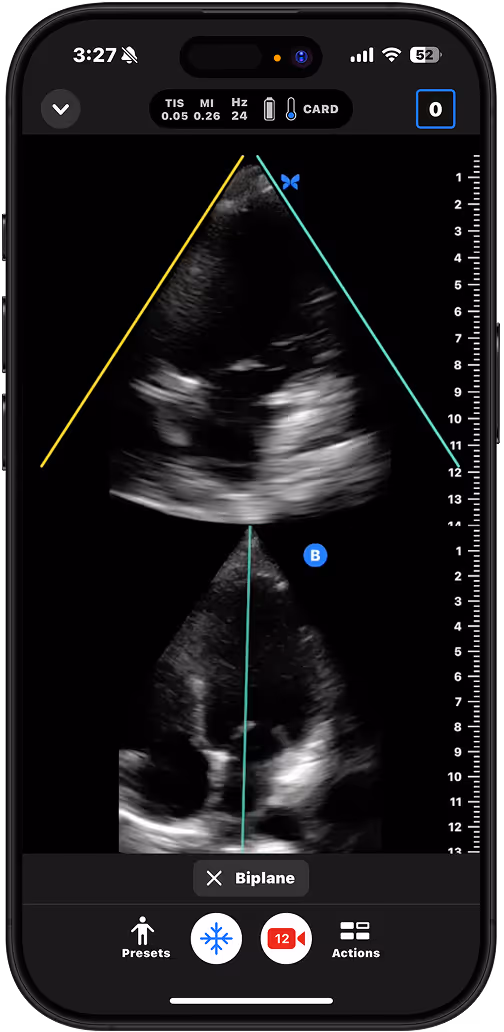

Assess for pericardial effusion or gross function in patients with chest pain or unexplained hypotension.